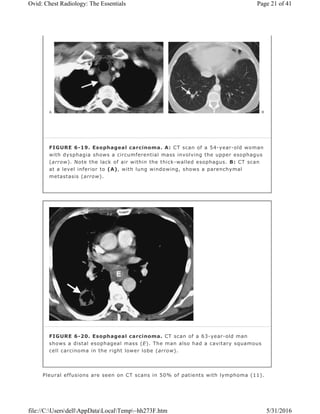

FIGURE 6-19. Esophageal carcinoma. A: CT scan of a 54-year-old woman

with dysphagia shows a circumferential mass involving the upper esophagus

(arrow). Note the lack of air within the thick-walled esophagus. B: CT scan

at a level inferior to (A), with lung windowing, shows a parenchymal

metastasis (arrow).

FIGURE 6-20. Esophageal carcinoma. CT scan of a 63-year-old man

shows a distal esophageal mass (E). The man also had a cavitary squamous

cell carcinoma in the right lower lobe (arrow).